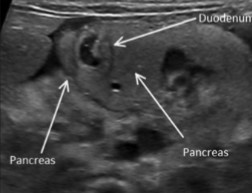

Label the crossed-out parts of this image.

IVC

Pancreatic head

SMV/Portal Confluence

Uncinate process

Right renal artery

Aorta

Splenic vein

Pancreatic tail

What 2 organs are mistakenly taken as the pancreas?

Stomach

Duodenum